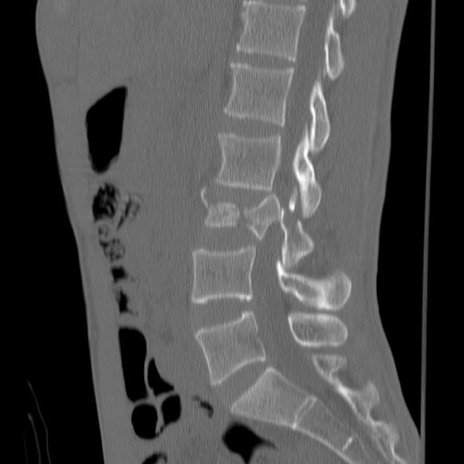

症例3 腰椎CT(矢状断像)

腰椎CT

異常所見と診断は?